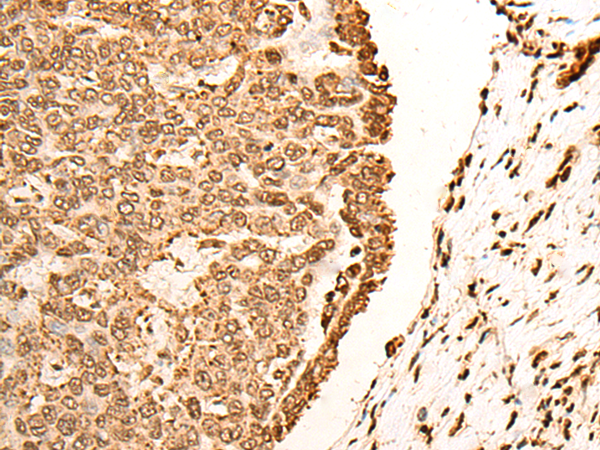

IHC positive control:

Human esophagus cancer and Human liver cancer

IHC Recommend dilution:

30-150